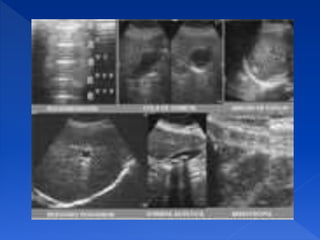

REVERBERANCIA

Presencia de múltiples líneas eco

génicas, paralelas.

Equidestantes y de intensidad

generalmente de crecientes, por

Detrás de una interfase con gran

cambio de impedancia acústica

UNA SOMBRA LIMPIA

Se produce cuando el haz ultrasónico

choca contra una superficie rugosa con

poco radio de curvatura, puede ser

producido por tejido cicatricial, septos

fibrosos normales, calcificaciones

dentro de los tejidos blandos y

superficies óseas.

LAS SOMBRAS SUCIAS

Se asocian con la presencia de gas, se

producen cuando un objeto de superficie

lisa con un gran radio (como una burbuja

de gas) rebota el sonido hacia atrás y

hacia delante del reflector muchas veces

(reverberación), entonces, los ecos que se

localizan profundos al reflector rellenarán

la sombra.

ARTEFACTO DE LÓBULOS LATERALES O

POR ÁNGULO CRÍTICO

Este artefacto se presenta cuando se

evalúan estructuras con superficies muy

curvas.

Una sombra se presenta en los bordes

laterales de la estructura, donde el haz

ultrasónico contacta la interfase (incluso

aunque no sea muy reflejante) en un

ángulo muy oblicuo.

ARTEFACTO EN ESPEJO

Estos artefactos pueden ser engañosos y si no

son reconocidos, resultan en un diagnóstico

incorrecto; afortunadamente, son muy raros en

la práctica diaria del ultrasonido.

El fenómeno de reverberación tiene lugar en

interfaces altamente reflejantes.

El sonido es rebotado en varias ocasiones

dentro del cuerpo, lo que trae como

resultado la formación de una imagen

fantasma o en espejo la cual se observa

como una estructura más profunda.